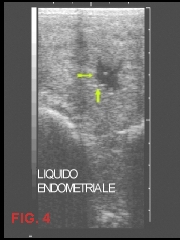

Una ridotta capacità di contrazione, un anomalo sfiancamento dell’utero, un lento ridimensionamento dell’organo, una ritenzione di placenta, non fanno altro che determinare accumulo di liquidi infiammatori all’interno del lume uterino (FIG. 4); e incapacità dello stesso ad eliminarli con i normali meccanismi fisiologici.